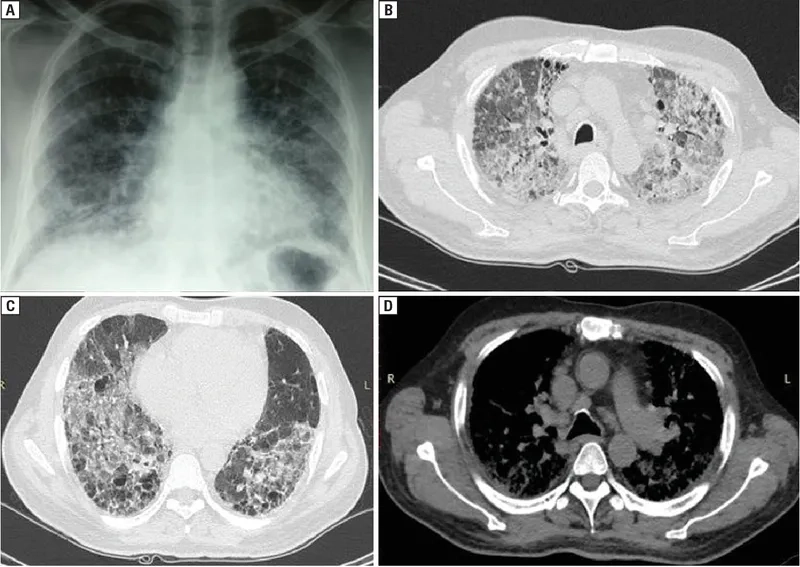

Addressing lung disease from dust exposure risks